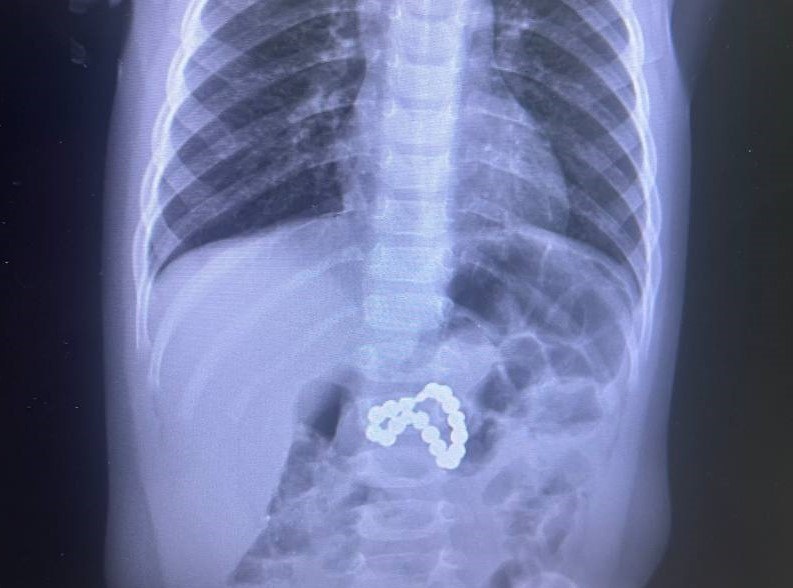

Врачи Сургута спасли девочку с магнитами в желудке

В Центр охраны материнства и детства в тяжелом состоянии поступил ребенок. Девочка проглотила магниты, результатом чего стало повреждение стенок желудка и кишечника. Это нередко приводит к летальному исходу. Ребенку требовалась срочная эндоскопия, сложная операция, ушивание перфорации, реанимация и переливание крови. Благодаря слаженной работе врачей, юную пациентку удалось спасли. Сейчас состояние ребенка стабильно, отмечается положительная динамика. «Выполнена экстубация, начато энтеральное питание, болевой синдром купирован. Впереди еще долгий путь восстановления», - отметили в медучреждении.